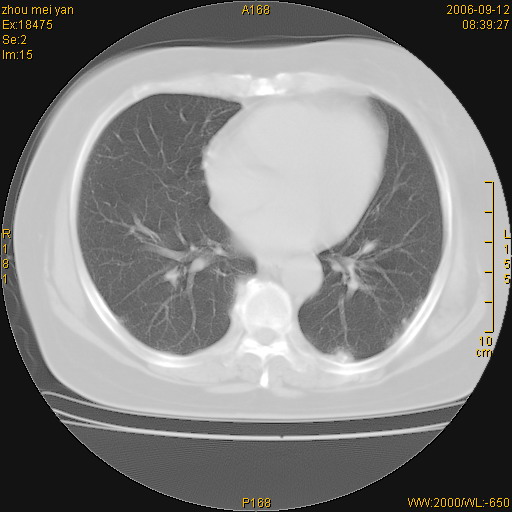

患者、女、55岁。因心率失常住院检查ct发现胸部多发结节。腹部b超肝、胆、胰、脾、肾、子宫附件未见异常。无结核病史,无粉尘接触史。请大家来会诊。谢谢!

病变位于胸膜,多发结节,边界清楚,内见小结节状钙化。其它未见异常。

双侧胸膜多发结节,形态不规则,边缘较清楚,每一个结节中心似乎都有钙化点的特征,与胸膜广基相切。临床无结核病史,无粉尘接触史。

影像表现十分有特点:双侧肋胸膜及膈胸膜广泛散在分布大小在2至6mm左右,较大病灶中心可见钙化。

双侧肋胸膜及膈胸膜广泛散在分布大小不等结节影,较大病灶中心可见钙化。